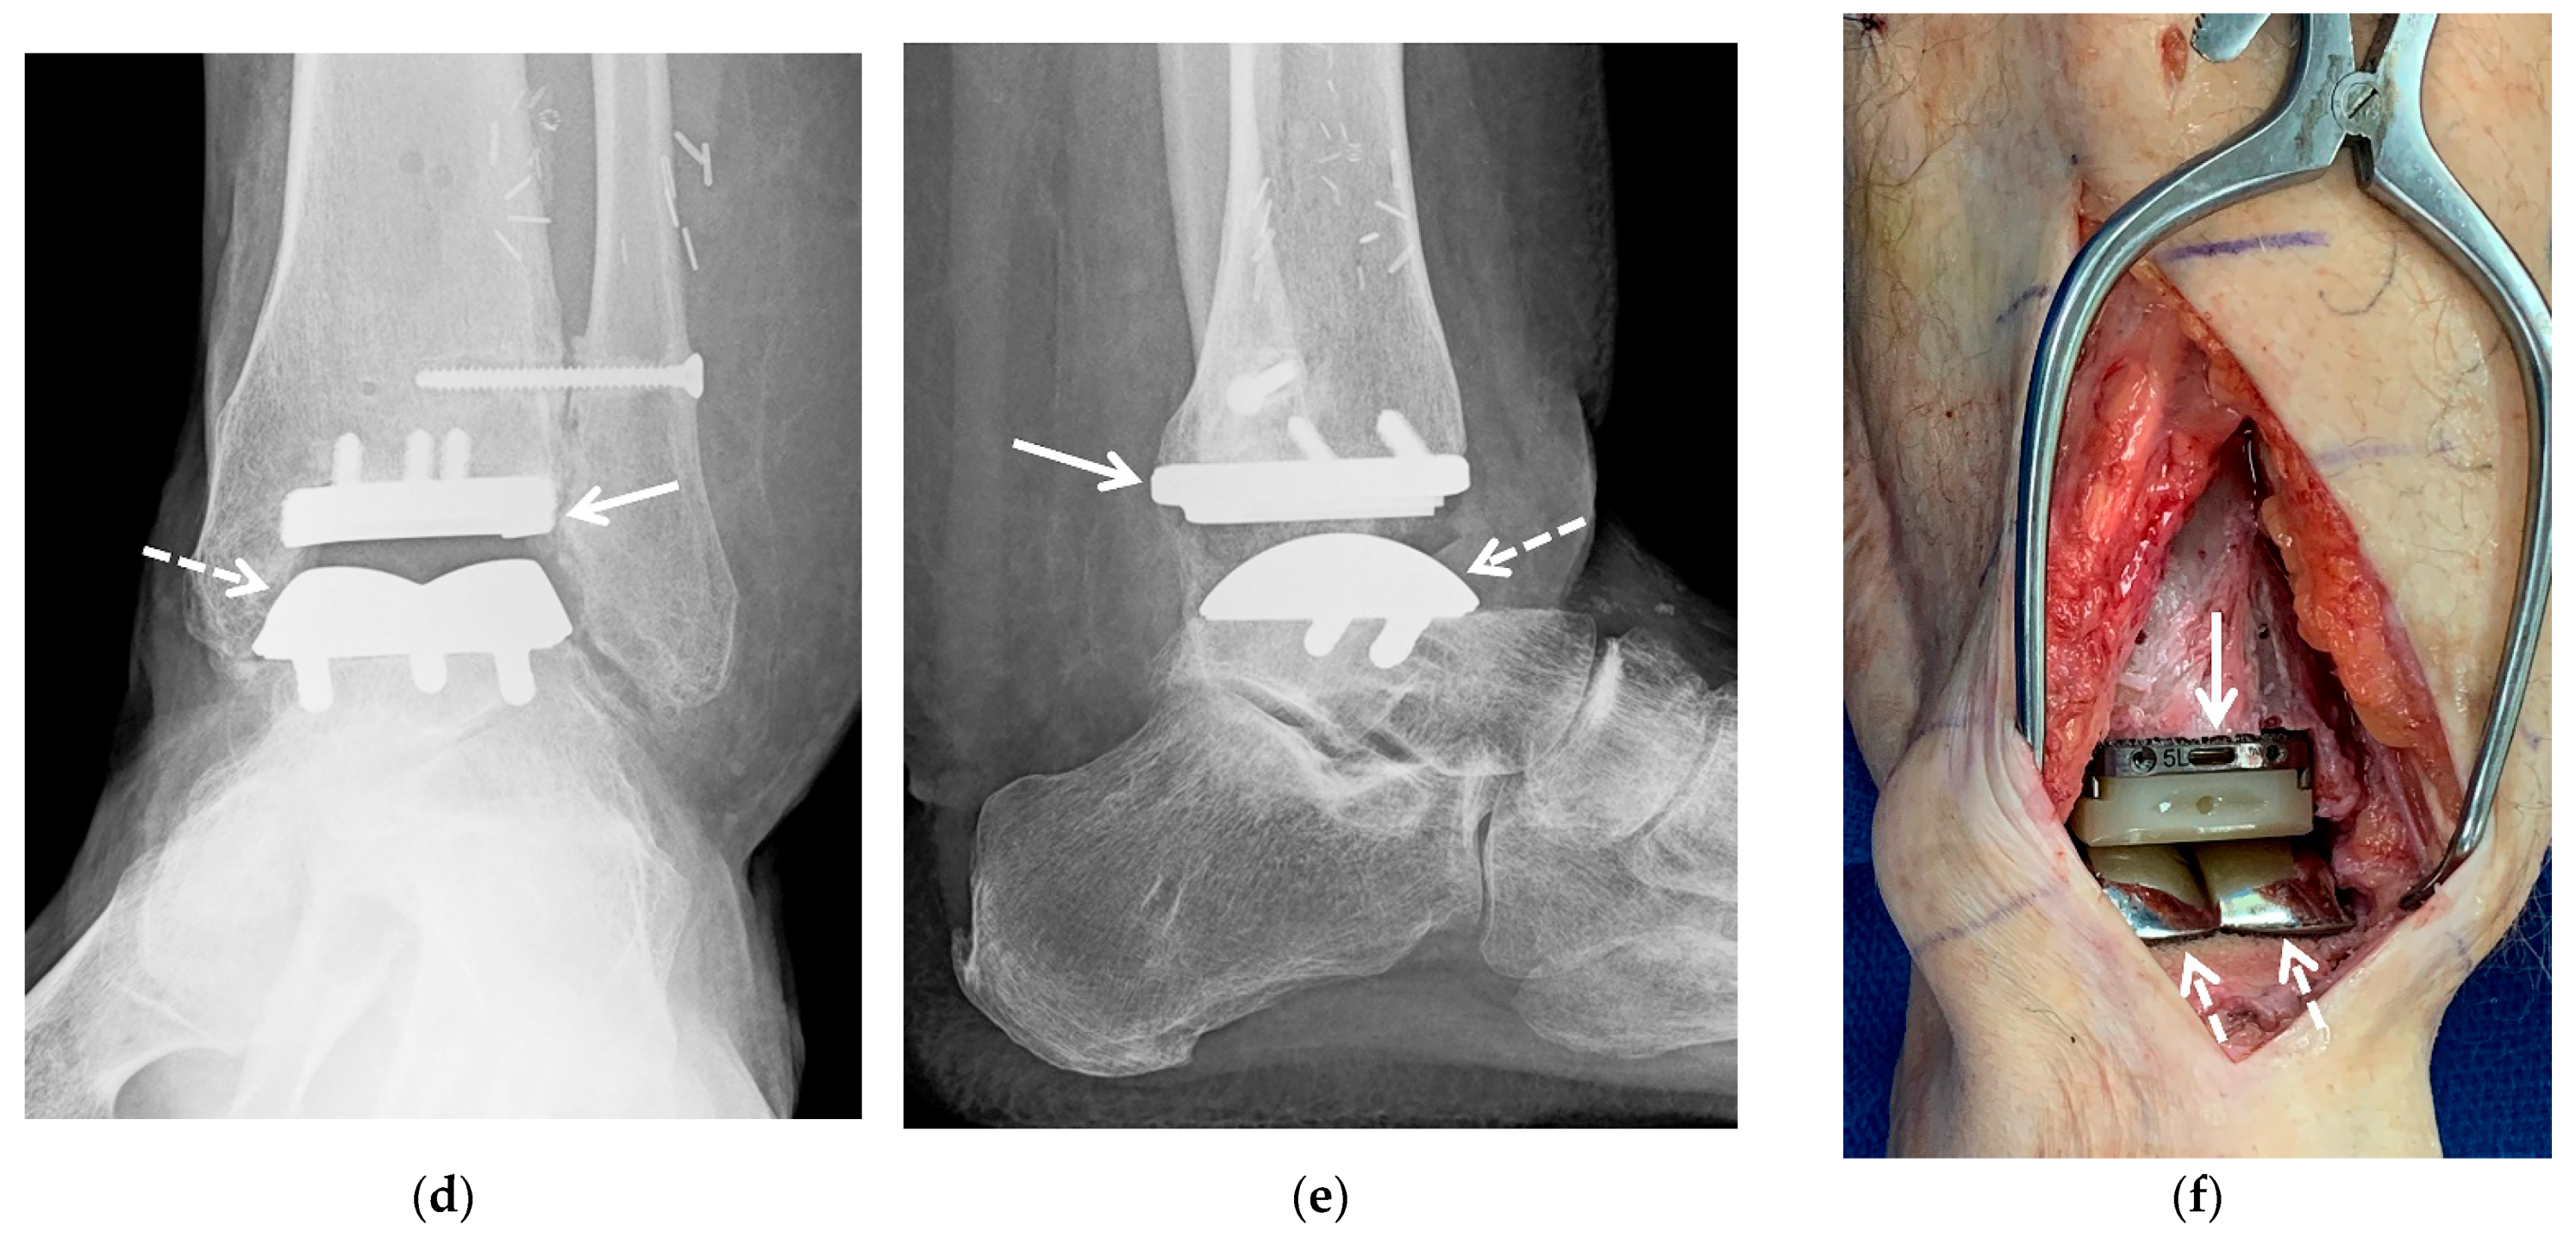

5.2.3. Ankle Arthroplasty